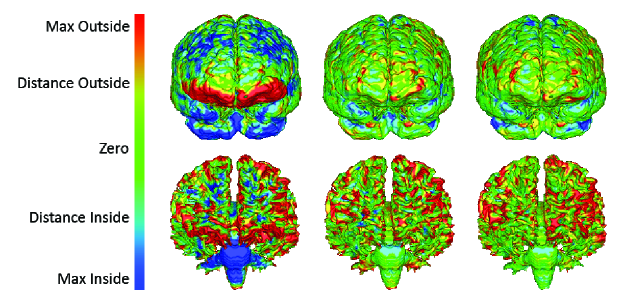

A primal-dual based optimization framework has been recently proposed in [127, 128] for the problem of deformable registration/fusion, which forms one of the most central and challenging tasks in medical image analysis. This problem consists of recovering a nonlinear dense deformation field that aligns two signals that have in general an unknown relationship both in the spatial and intensity domain. In this framework, towards dimensionality reduction on the variables, the dense registration field is first expressed using a set of control points (registration grid) and an interpolation strategy. Then, the registration cost is expressed using a discrete sum over image costs projected on the control points, and a smoothness term that penalizes local deviations on the deformation field according to a neighborhood system on the grid. One advantage of the resulting optimization framework is that it is able to encode even very complex similarity measures (such as normalized mutual information and Kullback-Leibler divergence) and therefore can be used even when seeking transformations between different modalities (inter-deformable registration). Furthermore, it admits a broad range of regularization terms, and can also be applied to both 2D-2D and 3D-3D registration, as an arbitrary underlying graph structure can be readily employed (see Fig. 11 for a result on 3D inter-subject brain registration).